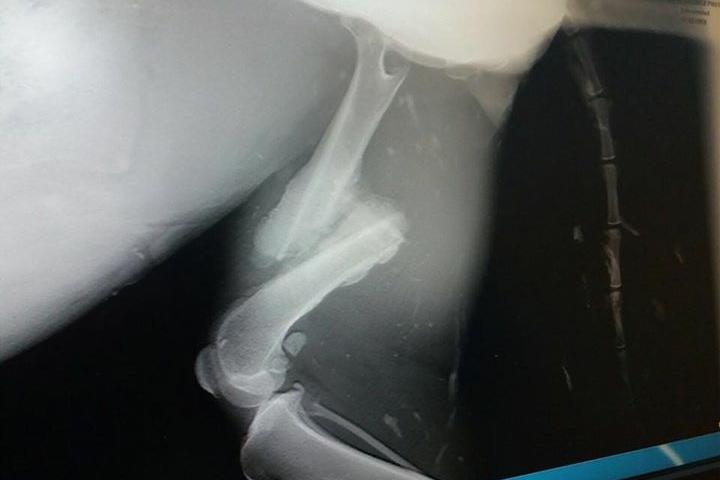

Lara-Border Collie con desprendimiento de retina y pata fracturada

Border Collie rescatada en muy mal estado. Ha perdido un ojo, tiene desprendimiento de retina y el hueso de una pata de atrás fracturado. Hay que operarla. La operación nos cuesta 773,98 euros. Necesitamos toda la ayuda posible para pagar la factura y para difundir a esta peque, y que encuentre pronto una familia que la quiera como se merece y pueda olvidar su pasado. Para realizar donaciones: Unicaja: ES55 2103 0459 03 0010008917 Titular es Qualidice, Protectora de Herencia Concepto: Ayud